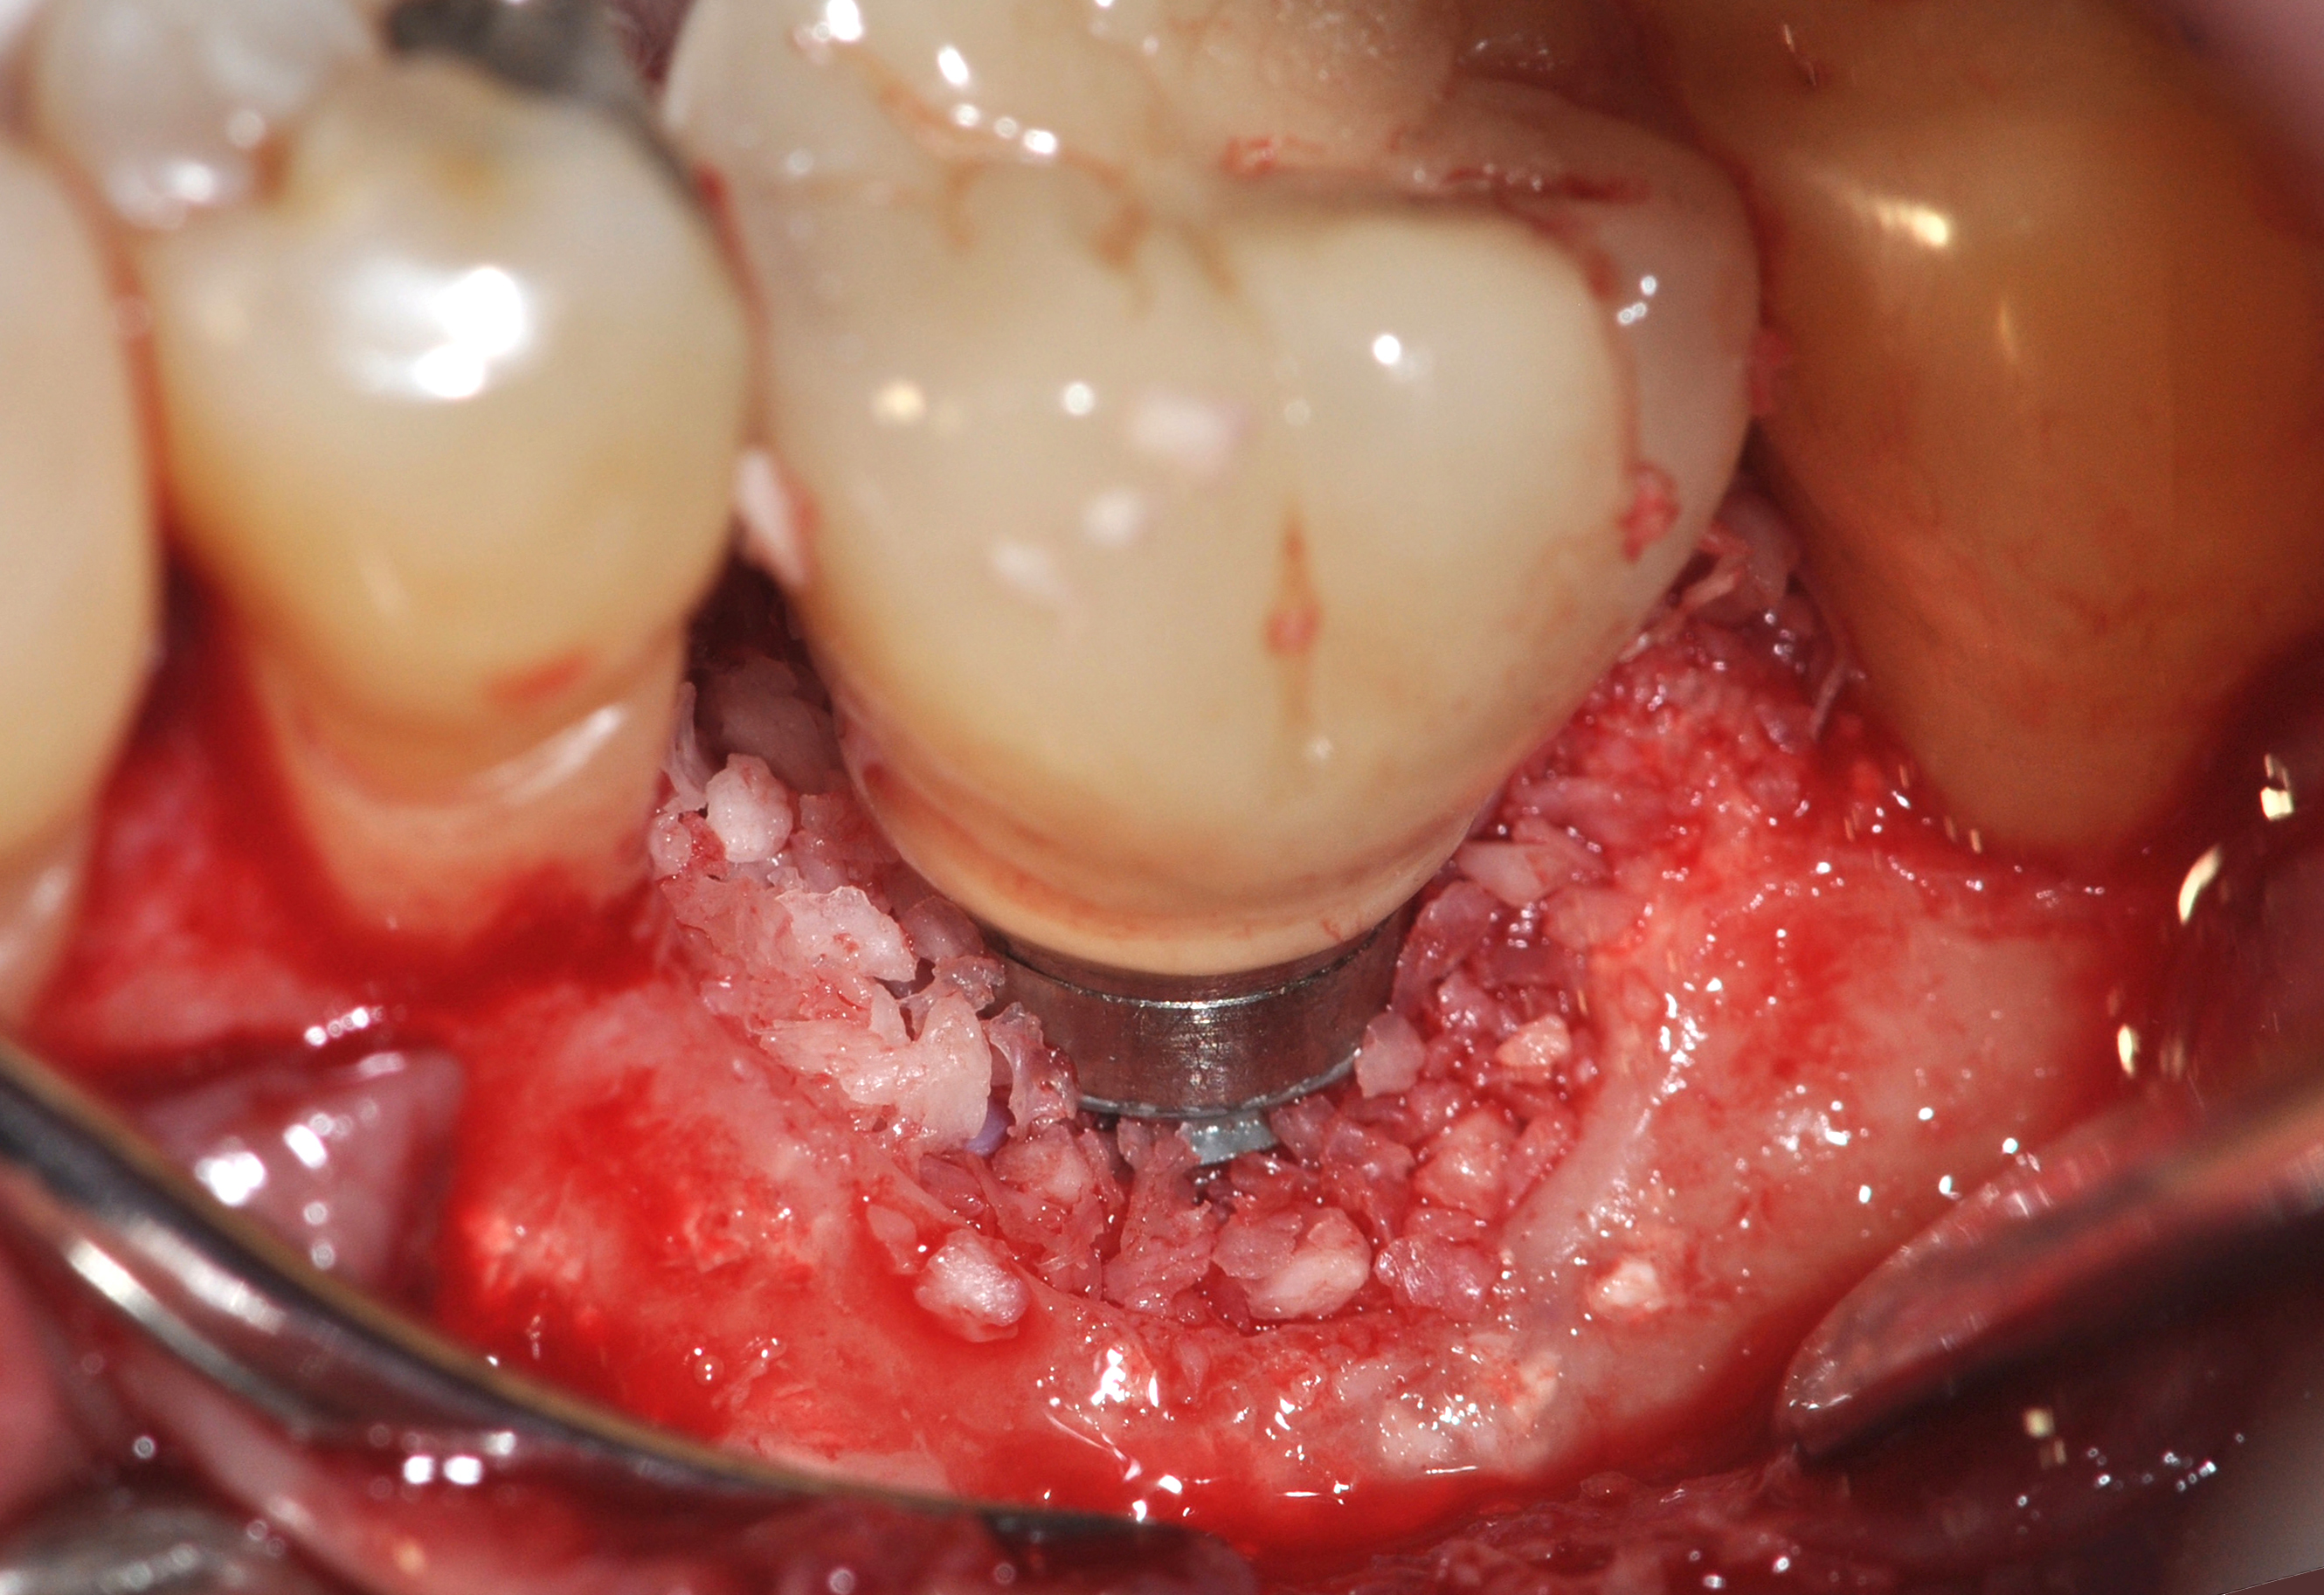

A surgical flap procedure was performed with the intent of thoroughly debriding the granulomatous tissue from the osseous defect (Figure 18 and Figure 19), mechanically and chemically detoxifying the surface of the implant (Figure 20 through Figure 22), and grafting the infrabony component of lesion with bone xenograft (Bio-Oss®, Geistlich Pharma, www.geistlich-na.com) in an attempt to reduce the vertical defect (Figure 23). To concurrently resolve the mucogingival problem, the plan called for placing a dermal allograft (Dermis Allograft, DENTSPLY International, www.dentsply.com) on the buccal (Figure 24) and then replacing the flap (Figure 25).

Fig 23. Fill of the infrabony defect with bone xenograft.

Figure 23

Fig 24. The bone graft was covered with dermis allograft that will act as a barrier to prevent epithelial downgrowth while simultaneously augmenting the vestibule and thin marginal gingiva that were contributing to the mucogingival problem.

Figure 24

Fig 43. A full thickness flap was raised to place a new 3.25-mm implant into tooth No. 26 area in a single-stage protocol.

Figure 43